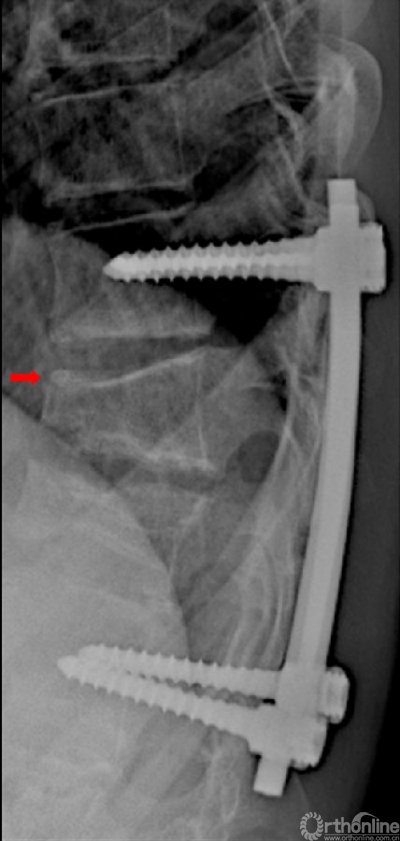

图4 患儿女,9岁,背部疼痛不适,术前胸椎侧位片,T8和T9椎体嗜酸性肉芽肿病变,椎体严重压缩变形。T8椎体上终板前缘骨骺破坏。

图5 术后胸椎侧位片,内固定位置良好。

图6 术后1年,T8、9椎体高度部分恢复,T8椎体前缘恢复有限(箭头)